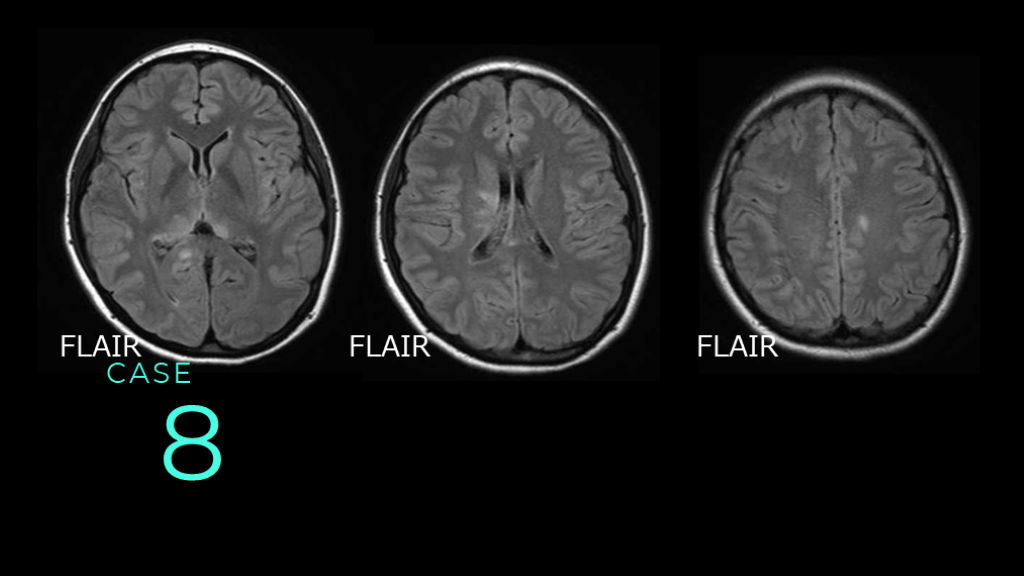

8 CASE FLAIR FLAIR FLAIR

8 CASE DWIでは信号変化がないので、FLAIRのみ提示。 基底核レベルのスライスで、左側脳室近傍の高信号変化あり。放線冠レベルのスライスでも、右側脳室に沿った高信号病変あり。前頭葉白質にも斑状高信号病変あり。

8 CASE コメント:多発性硬化症の症例。他の撮像条件で信号変化が特になかったので、1つ提示するならFLAIRをみせよう、という症例。